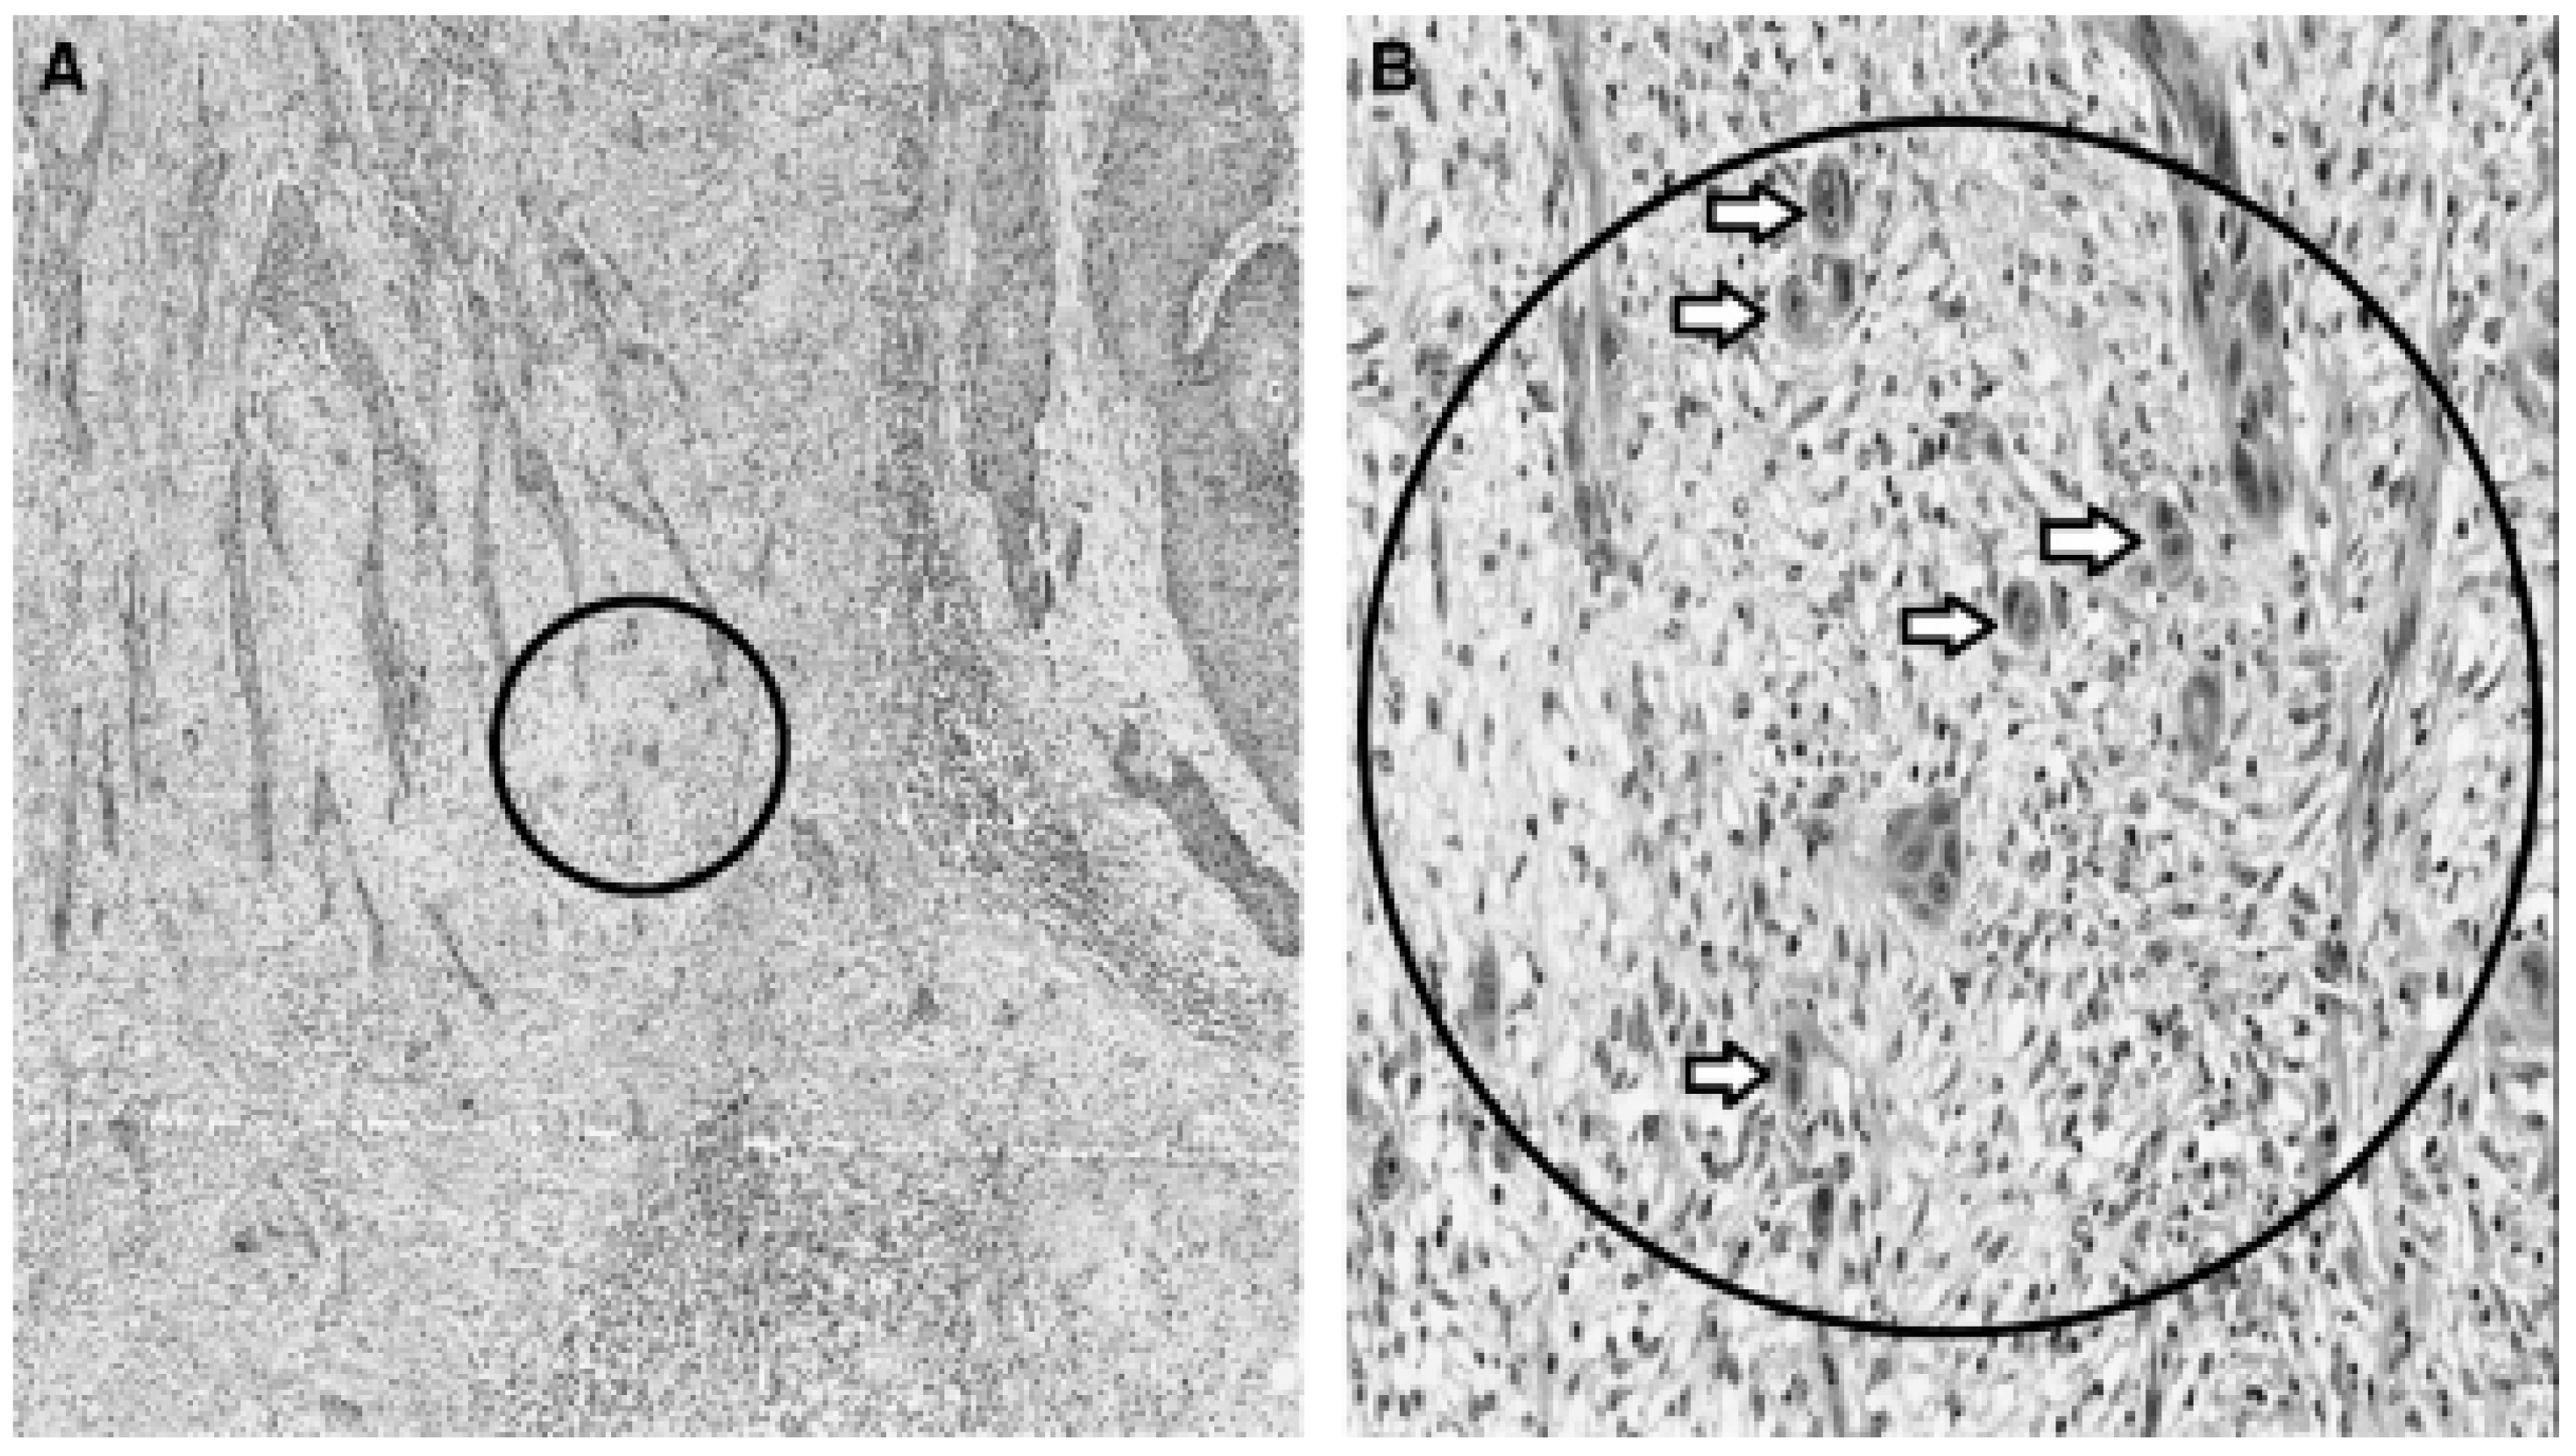

Oral cancer

- Almangush, A.; Pirinen, M.; Heikkinen, I.; Mäkitie, A.A.; Salo, T.; Leivo, I. Tumour budding in oral squamous cell carcinoma: a meta-analysis. British journal of cancer 2018, 118, 577–586. [Google Scholar] [CrossRef]